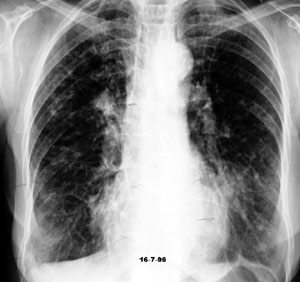

- Al menos dos de los siguientes criterios adicionales: a. Anticuerpos séricos precipitantes contra el antígeno de Aspergillus o IgG de Aspergillus en suero elevado por inmunoensayo: La detección de anticuerpos específicos contra Aspergillus en suero, como los anticuerpos precipitantes o IgG elevada, respalda el diagnóstico. b. Anomalías radiográficas pulmonares consistentes con ABPA: La presencia de hallazgos radiográficos específicos en la tomografía computarizada de tórax, como opacidades bronquiales y consolidaciones mucoides, es característica de la ABPA. c. Recuento de eosinófilos en sangre periférica superior a 500 células/mcL (mayor de 0,5 × 109/L): La eosinofilia periférica es común en la ABPA debido a la respuesta inmune tipo Th2 asociada con la liberación de citocinas y quimiocinas que reclutan eosinófilos a los tejidos inflamados.

Las anomalías radiográficas incluyen opacidades transitorias, impactación mucoide y bronquiectasis proximal o central.